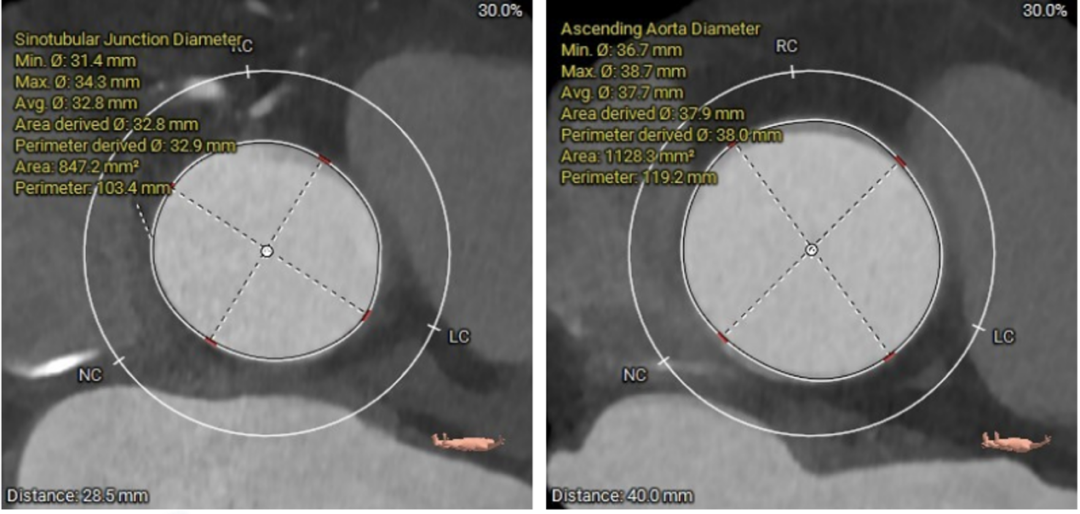

图2. 瓦氏窦、STJ内径稍大,升主动脉轻微扩张,升主最宽处42.3mm

图3. 左冠高度:18.4mm  右冠高度:19.8mm